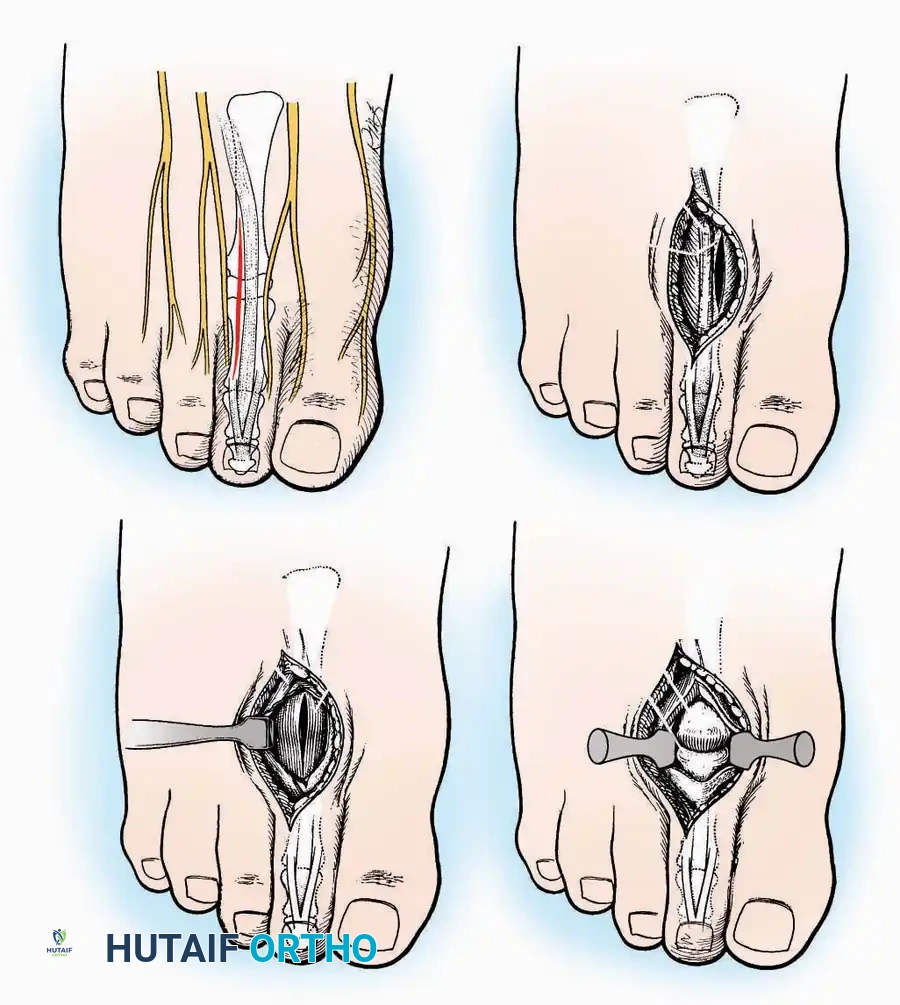

Approaches to the Metatarsophalangeal (MTP) Joint of the Great Toe

The first MTP joint is the epicenter of forefoot reconstructive surgery. Exposure can be achieved via medial or dorsomedial trajectories.

Medial Approach

Indications: Hallux valgus correction (bunionectomy), first MTP arthrodesis, or cheilectomy.

Surgical Technique:

* Incision: Make a curved incision 5 cm long on the medial aspect of the joint. Begin just proximal to the IP joint, curve it over the dorsum of the MTP joint (medial to the extensor hallucis longus [EHL] tendon), and terminate on the medial aspect of the first metatarsal 2.5 cm proximal to the joint.

* Superficial Dissection: As the deep fascia is incised, identify and laterally retract the medial branch of the first dorsal metatarsal artery and the medial branch of the dorsomedial nerve (a terminal branch of the superficial peroneal nerve).

* Deep Dissection: Dissect the fascia from the dorsum down to the bursa overlying the medial eminence of the metatarsal head.

* Capsulotomy: Make a curved incision through the bursa and joint capsule. Begin dorsomedially, continue proximally dorsal to the metatarsal head, sweep plantarward, and end distally on the medioplantar aspect of the joint. This creates an elliptical, racquet-shaped flap attached at the base of the proximal phalanx.

⚠️ Surgical Pitfall

While distal reflection of this racquet flap provides ample exposure of the first MTP joint, the extensive subfascial undermining required can compromise the vascularity of the skin flap, leading to delayed healing or necrosis. Consequently, the dorsomedial approach is often preferred in modern practice.

Dorsomedial Approach

Indications: Preferred approach for primary and revision first MTP arthroplasty, arthrodesis, and complex bunion corrections due to superior angiosome preservation.

Surgical Technique:

* Incision: Begin just proximal to the IP joint and extend proximally for 5 cm, running parallel and strictly medial to the EHL tendon.

* Exposure: Divide the superficial fascia. Identify and retract the EHL tendon laterally.

* Capsulotomy: The capsule can be incised longitudinally in the exact plane of the skin incision, allowing for subperiosteal elevation of the capsule medially and laterally, preserving the vascular supply to the medial skin flap.